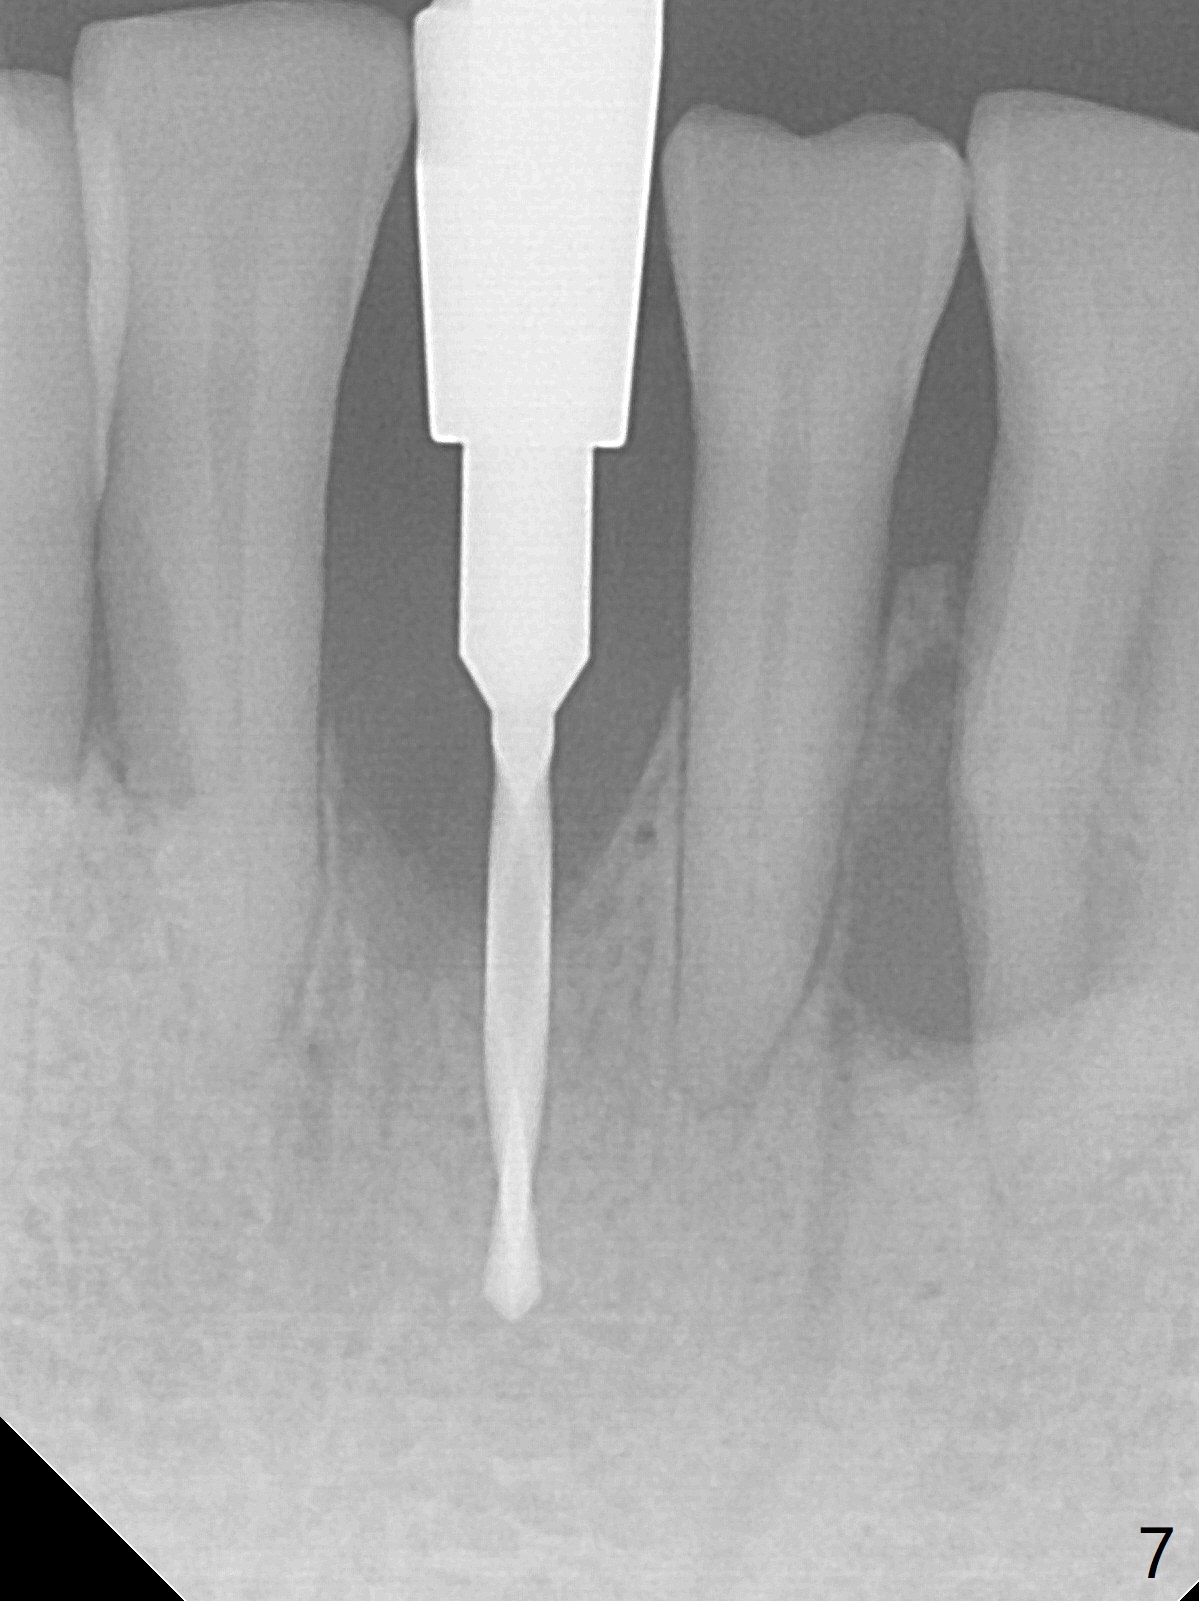

There is gingival inflammation at #25 buccally (Fig.1) and lingually (Fig.2). The bone loss is severe (Fig.3). Soft and hard tissue heights are 5 mm (cuff will be 4 mm) and 10 mm (implant will be 12 mm with 2 mm outside the native bone, Fig.4). The apex of the affected tooth appears deviated distal (Fig.5 *). The initial osteotomy happens to follow the long axis of the socket (Fig.6); to establish a correct trajectory, a new osteotomy should be made at the site labeled as a red line. In fact it is executed as planned (Fig.7). Because of the narrow flat ridge buccolingually, a 2.5x12(4) mm 1-piece implant is placed with >40 Ncm (Fig.8). With deeper placement of the implant, Vanilla graft is placed in 2 steps (Fig.9,10). The patient will return 2.5 months for extraction and implant of the fused teeth #22 and 23. No implant threads are exposed 10 months postop (Fig.11). CT taken 11 months postop shows that the 2.5 mm implant is in the middle of the bone (Fig.12) or 2 years post cementation (Fig.13).